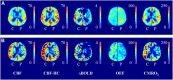

The purpose of this study was to assess whether calibrated magnetic resonance imaging (MRI) can identify regional variances in cerebral hemodynamics caused by vascular disease. For this, arterial spin labeling (ASL)/blood oxygen level-dependent (BOLD) MRI was performed in 11 patients (65±7 years) and 14 controls (66±4 years). Cerebral blood flow (CBF), ASL cerebrovascular reactivity (CVR), BOLD CVR, oxygen extraction fraction (OEF), and cerebral metabolic rate of oxygen (CMRO2) were evaluated. The CBF was 34±5 and 36±11 mL/100 g per minute in the ipsilateral middle cerebral artery (MCA) territory of the patients and the controls. Arterial spin labeling CVR was 44±20 and 53±10% per 10 mm Hg ▵EtCO2 in patients and controls. The BOLD CVR was lower in the patients compared with the controls (1.3±0.8 versus 2.2±0.4% per 10 mm Hg ▵EtCO2, P<0.01). The OEF was 41±8% and 38±6%, and the CMRO2 was 116±39 and 111±40 μmol/100 g per minute in the patients and the controls. The BOLD CVR was lower in the ipsilateral than in the contralateral MCA territory of the patients (1.2±0.6 versus 1.6±0.5% per 10 mmHg ▵EtCO2, P<0.01). Analysis was hampered in three patients due to delayed arrival time. Thus, regional hemodynamic impairment was identified with calibrated MRI. Delayed arrival artifacts limited the interpretation of the images in some patients.